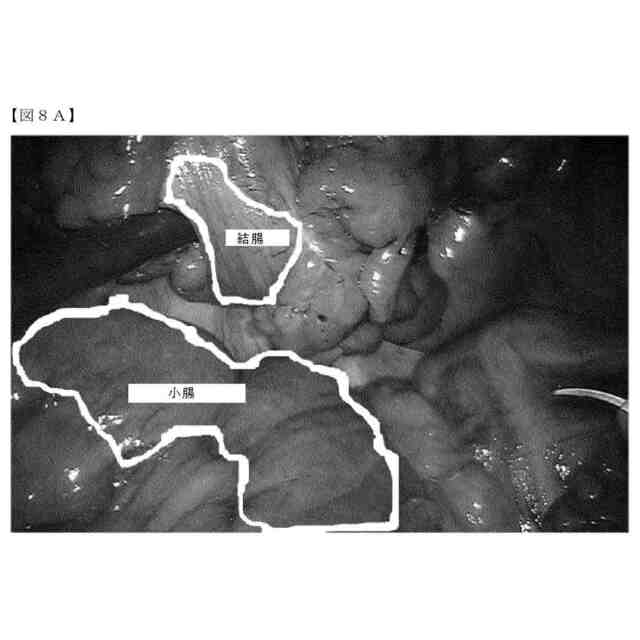

第一の実施形態では、本開示は、従って、対象の解剖学的構造の、例えば、外科手術等の医療処置中の自動灌流評価のためのシステムに関する。システムは、対象の血中への所定量の蛍光造影剤の注入を制御するように構成され得る。注入は、システムの制御下にあることができる、制御可能な注入ポンプによって行うことができる。注入ポンプは、システムの一部であってよく、システムは、少なくとも1つの蛍光造影剤を保持するための少なくとも1つの制御可能な注入ポンプを含む。すなわち、この注入ポンプは、所定量の当該蛍光造影剤を対象の血中に注入するように構成され得る。好ましくは、システムは、所定量の当該蛍光造影剤が一定間隔及び/または所定の間隔で繰り返し注入されるように構成される。システムはさらに、蛍光造影剤の注入後の当該解剖学的構造の組織の時系列の蛍光画像、別名、映像を受信及び分析するように構成され得る。この分析に基づいて、当該解剖学的構造の少なくとも1つの灌流パラメータを特定することができる。

本開示のシステムは、それ故、さらに、蛍光造影剤の最初の少量のボーラスを注入するように注入ポンプを制御し、その後、この最初のボーラスから生じる蛍光発光を分析するように構成され得る。この最初の少量のボーラスは、好ましくは、生理食塩水でのフラッシングと組み合わせ、状況、すなわち、使用される蛍光剤のタイプ、及び患者の形態、例えば、年齢、体重、身長等に応じて選択する必要がある。しかしながら、対象の体重の0.01mg/kg未満の量、すなわち、50kgの患者に対しては0,5mg未満及び100kgの患者に対しては1mg未満が、特に、ICGが使用される場合に通常望ましい開始点である。

本発明者らは、解剖学的構造の組織からの定量化可能な蛍光発光が、例えば、コンピュータ画像分析を使用することによって、人間の目に見える蛍光発光よりもはるかに小さいことに気付いた。すなわち、蛍光信号強度は、外科医による目視検査によってではなく、コンピュータによる画像認識及び画像分析によって測定可能な大きさが必要なだけであるため、はるかに少ない用量、例えば、マイクロドーズが可能である。すなわち、マイクロドーズの蛍光剤を対象に投与することができ、例えば、灌流パラメータをそれから特定することができる。